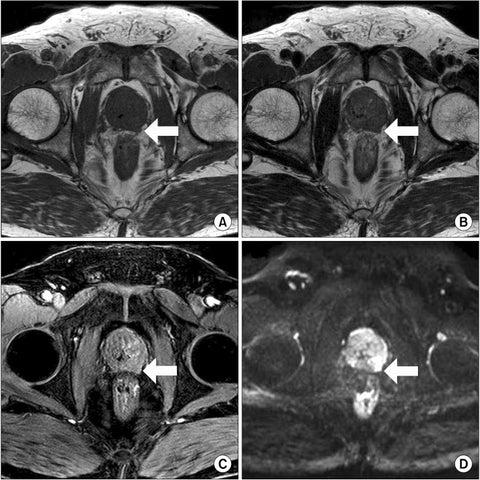

Changes in the prostate as you age

Because the prostate gland tends to grow larger with age, it may squeeze the urethra and cause problems in passing urine. Sometimes men in their 30s and 40s may begin to have these urinary symptoms and need medical attention. For others, symptoms aren't noticed until much later in life. An infection or a tumor can also make the prostate larger.

Reducing Inflammation: Prostate problems are frequently linked to inflammation within the prostate gland. The capsules contain a unique blend of natural compounds renowned for their potent anti-inflammatory properties. By targeting and reducing inflammation in the prostate, these capsules help alleviate pain, discomfort, and swelling associated with prostate issues. Interferes with the production or activity of inflammatory mediators, such as cytokines and prostaglandins. By doing so, they help modulate the inflammatory response, resulting in a decrease in inflammation and swelling.